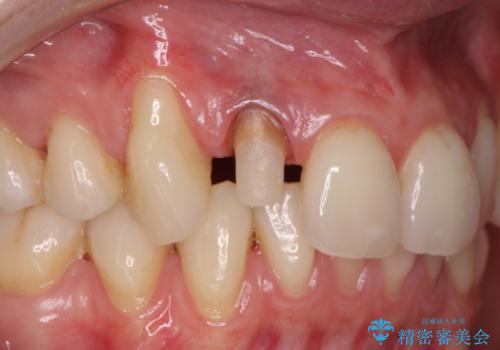

- 右上前歯の形と色が気になるとのことで来院された患者様です。

残っている歯に亀裂が多く走っていたため、クラウンでの修復処置を行います。

歯ぐきの扱いに気を付けることで、術前よりも歯ぐきの位置が改善されました。